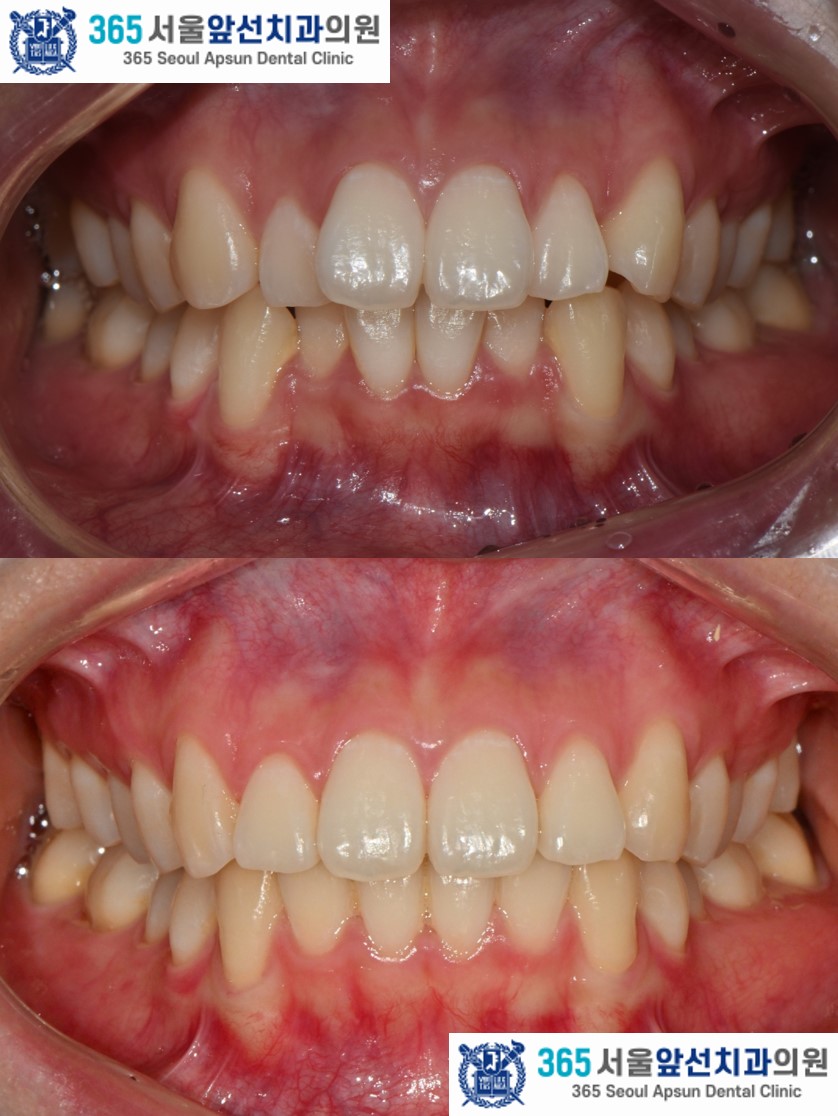

앞니의 비뚤한 치열을 고민으로 내원하신 20대 여성 환자 분의 증례를 소개드리겠습니다. 치료 전의 모습입니다. 상,하악 치열 각각 3.1mm, 2.9mm 의 필요 공간이 있는 중등도의 총생(Crowding)이 관찰됩니다. (그림2) 촬영일자 2025.02.25.

아랫니의 치열이 윗니의 치열보다 후퇴되어있는 2급 부정교합도 있었지만, 환자분은 2급 부정교합은 수정하지 않고 앞니의 치열만 가지런히 하기를 원하셔서 부분 교정으로 진행하였습니다. 이 경우, 2급 부정교합과 수평 피개는 잔존하게 됩니다. 부정교합의 정도에 따라, 치료계획을 좀더 간단하게 수정할 수 있습니다. 전체 교정과 부분 교정의 계획은 꼭 전문의와의 상담을 통해 결정하는 것이 좋습니다. ^^ (그림3) 촬영일자 2025.11.06.